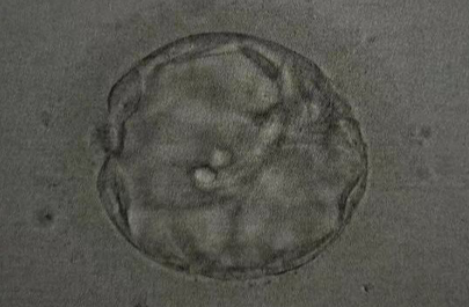

胚胎发育结果

取卵及受精

• 取卵:6颗

• 成熟MII:6颗

• ICSI受精:4颗

• 养囊成功:2颗

▲ Z女士的养囊报告

PGT-A染色体筛查结果

• 2 枚囊胚送检,2 枚过筛 - 适合移植

▲ Z女士的胚胎筛查报告